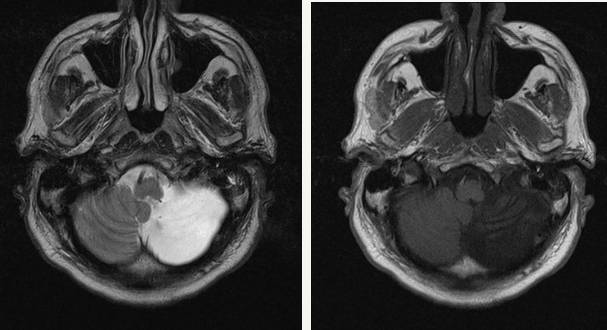

МРТ: головные боли после получения травмы. Постишемические кистозно-атрофические изменения: ишемический инфаркт левого полушария мозжечка в стадии поздней организации